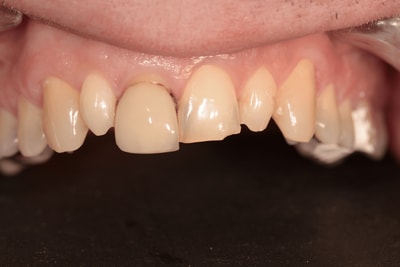

Situation Initiale